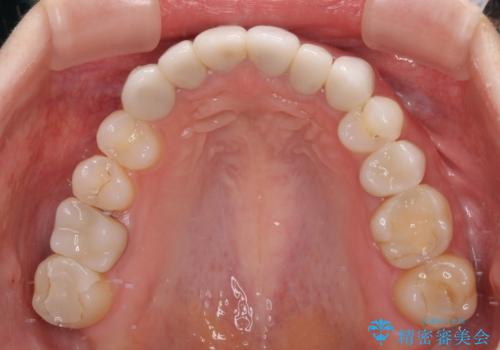

- 上下前歯のデコボコと奥歯の欠損を気にして来院された患者様です。

右下の欠損分は奥歯が倒れ込んでスペースがなくなっていたため、矯正治療により本来の位置に歯を移動させ、オールセラミックブリッジによる欠損補綴治療を行うこととしました。

全顎的にセラミッククラウンが多く装着されているため、インビザラインによる矯正治療を行うこととしました。

右下は移動量が多いため、十分な移動が達成されない場合はワイヤー装置を使用する予定としておりましたが、しっかりとマウスピースを装着してくださったため、前歯とともに十分に歯を動かすことができました。